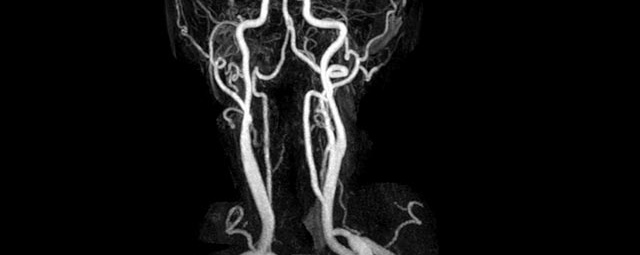

• intrakranielle Gefäße (Abklärung Verschluss, Stenose, Aneurysma)

• Halsgefäße zur Therapieplanung (z.B. Stent, Operation)

MR-Angiografie (MRA)

• MR-Angiografie ohne Kontrastmittel

• Time of Flight (TOF)-Angiographie

Je nach Fragestellung und Körperregion Gefäßdarstellung ohne Kontrastmittel bei Kontrastmittelunverträglichkeit oder terminaler Niereninsuffizienz möglich.

• MR-Angiographie mit Kontrastmittel

• Erfassung arterieller und venöser Gefäße/Bypässe aller Körperregionen mit 3D-Rekonstruktion